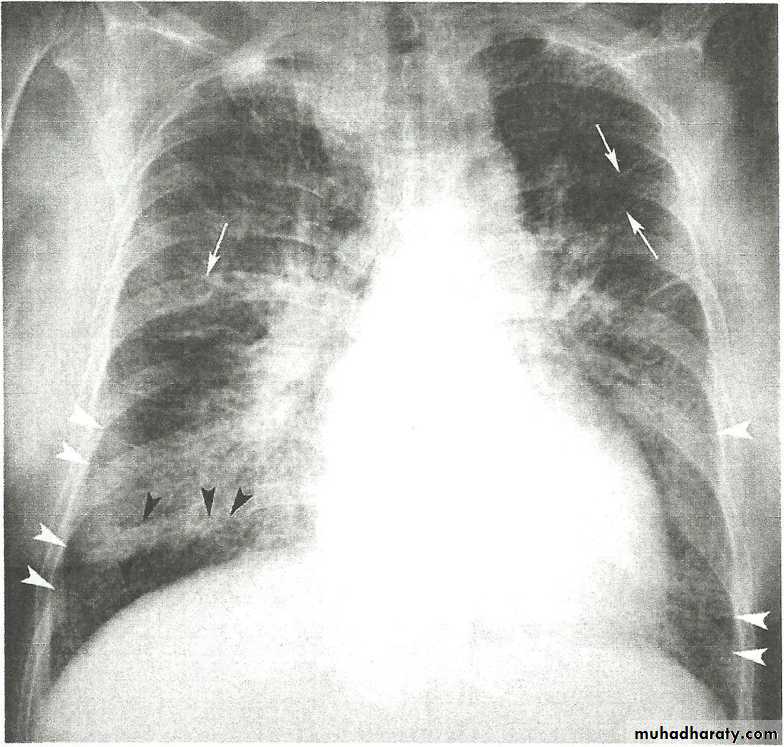

• Alveoiar oedema (‘Bat’s wings’)

• Kerlev B lines (interstitial oedema)

• Prominent upper lobe vessels

• Cardiomegaiy

• Pleura

• effusion

Kerley A lines (Arrows), Kerley B lines (arrowheads)